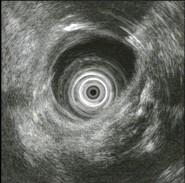

问题 女,55岁,腹痛便秘8年,大便干结伴排便不尽感,35天一次大便,无脓血便及恶心呕吐,食纳如常,体检无异常,结肠镜检查如图。患者哪种疾病可能性最大 ( )

选项 A、肠结核 B、溃疡性结肠炎 C、肠易激综合征 D、肠梗阻 E、结肠癌

答案 C